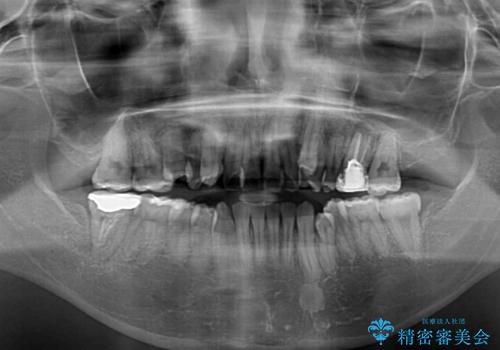

- 咬み合わない前歯と八重歯などのデコボコを気にして来院された患者様です。

上下前歯の位置を比較すると上顎が前方にあり、デコボコ改善でより上顎が前方に行く可能性があります。

開咬の改善にはインビザラインが有効であり、インビザライン単体での治療を検討しましたが、上顎前突を回避するために上顎左側第一小臼歯抜歯を行うこととしたため、補助装置とワイヤー矯正を併用した上で、インビザラインによる矯正治療を行うこととしました。